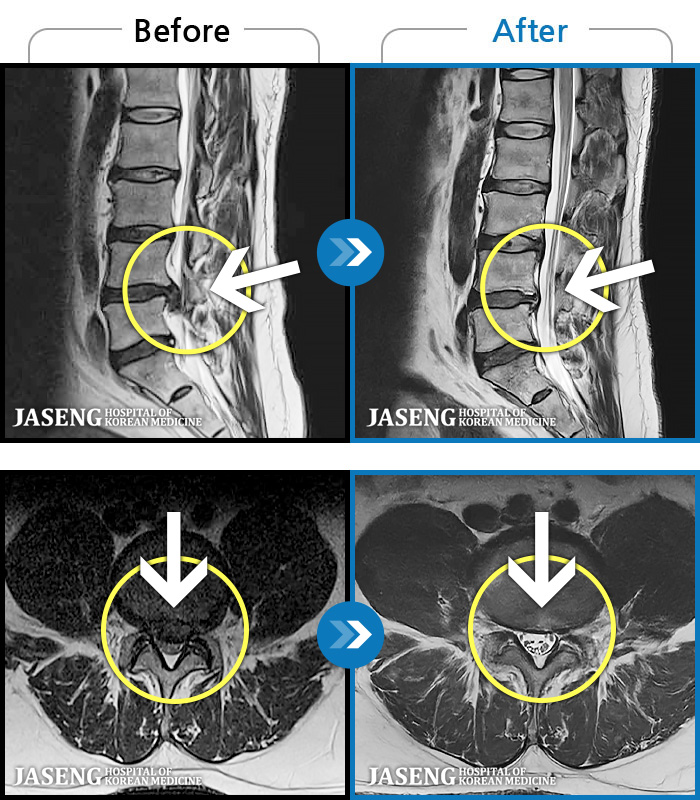

MRI ġ

1,237 MRI ũ ʸ Ȯϼ.